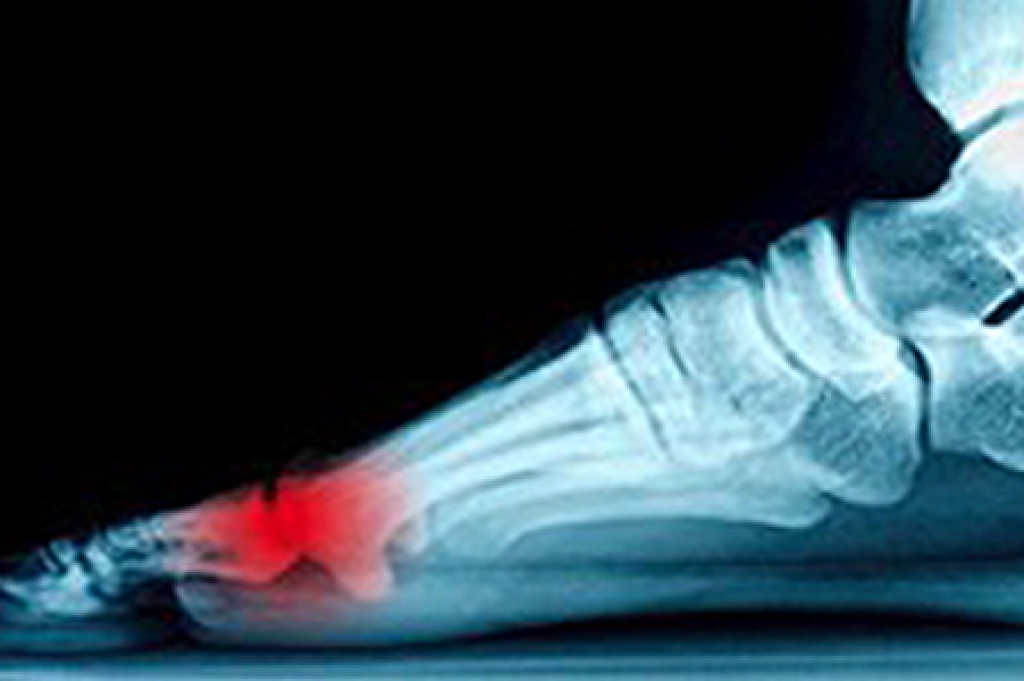

A foot ulcer is an open sore that can affect the surface skin or extend deep enough to reach tendons, bones, or other structures. People with diabetes, poor circulation, nerve damage, or foot deformities face a higher risk of developing ulcers. Nerve damage can make it hard to notice injuries like cuts or pressure spots, especially when wearing shoes that rub against the skin. Poor circulation slows healing by limiting the oxygen that reaches tissues in the foot. If left untreated, a foot ulcer may become infected, sometimes leading to an abscess, cellulitis, or a bone infection. In severe cases, it can cause tissue death or result in limb loss. Early care by a podiatrist focuses on diagnosing the cause of the ulcer, removing dead tissue, if needed, and helping to prevent infection. If you have developed a foot ulcer that will not heal, it is suggested that you schedule an appointment with a podiatrist for an exam and appropriate treatment options.